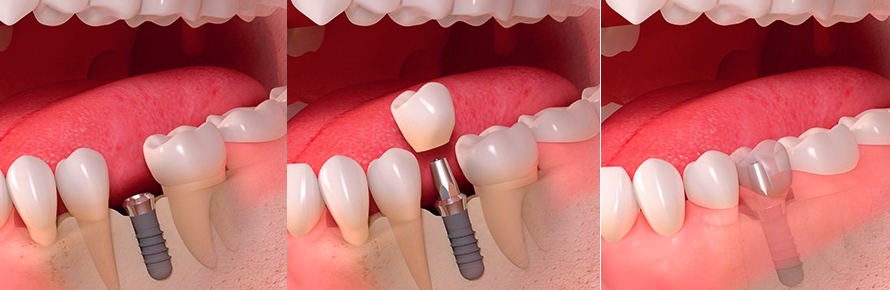

Стоматология «5 Принципов» в Симферополе гордится своими достижениями в области имплантации и постоянного совершенствования качества обслуживания. Наши клиенты получают индивидуально подобранные решения, основанные на передовых технологиях, годах опыта и внимании к деталям. Мы предлагаем комплексный подход: от подробной консультации до восстановления жевательной функции и эстетики улыбки.Каждый этап начинается с точной диагностики: цифровая томография, планирование в 3D, моделирование улыбки. Это позволяет увидеть предполагаемые результаты до начала операции и минимизировать риски.

При имплантации мы используем современные системы имплантатов с высоким процентом приживления и минимальным временем восстановления. Наши специалисты владеют техниками одномоментной фиксации и протезирования без необходимости временной съемной конструкции, что обеспечивает быструю адаптацию и комфорт пациента.В портфолио клиники — примеры успешных восстановлений: имплантация одиночного зуба с естественным оттенком коронки, комплексная реконструкция зубного ряда, а также имплантация с последующим использованием циркониевой коронки для максимальной эстетики. Мы уделяем внимание функциональности, долговечности и гармонии с природной линией улыбки.Послеоперационное сопровождение — важная часть our подхода: контроль за имплантатами, профилактические процедуры и рекомендации по уходу. В «5 Принципы» мы стремимся вернуть уверенность и комфорт улыбке каждого клиента в Симферополе.